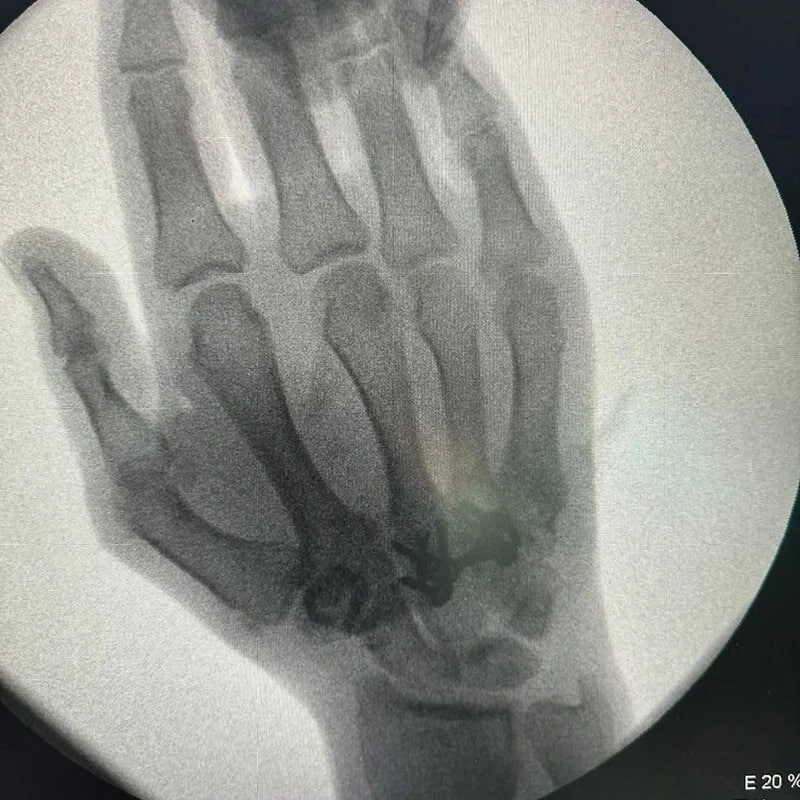

πŸ₯ˆπŸ₯‹ БСрСбряный ΠΏΡ€ΠΈΠ·Π΅Ρ€ Π»Π΅Ρ‚Π½ΠΈΡ… ΠžΠ»ΠΈΠΌΠΏΠΈΠΉΡΠΊΠΈΡ… ΠΈΠ³Ρ€ 2020 Π³ΠΎΠ΄Π° Π² Π’ΠΎΠΊΠΈΠΎ каратист Π Π°Ρ„Π°ΡΠ»ΡŒ АгаСв пСрСнСс ΠΎΠΏΠ΅Ρ€Π°Ρ†ΠΈΡŽ Π½Π° Ρ€ΡƒΠΊΠ΅

По словам спортсмСна, Π² настоящСС врСмя ΠΎΠ½ чувствуСт сСбя Ρ…ΠΎΡ€ΠΎΡˆΠΎ, опСрация ΠΏΡ€ΠΎΡˆΠ»Π° ΡƒΡΠΏΠ΅ΡˆΠ½ΠΎ.